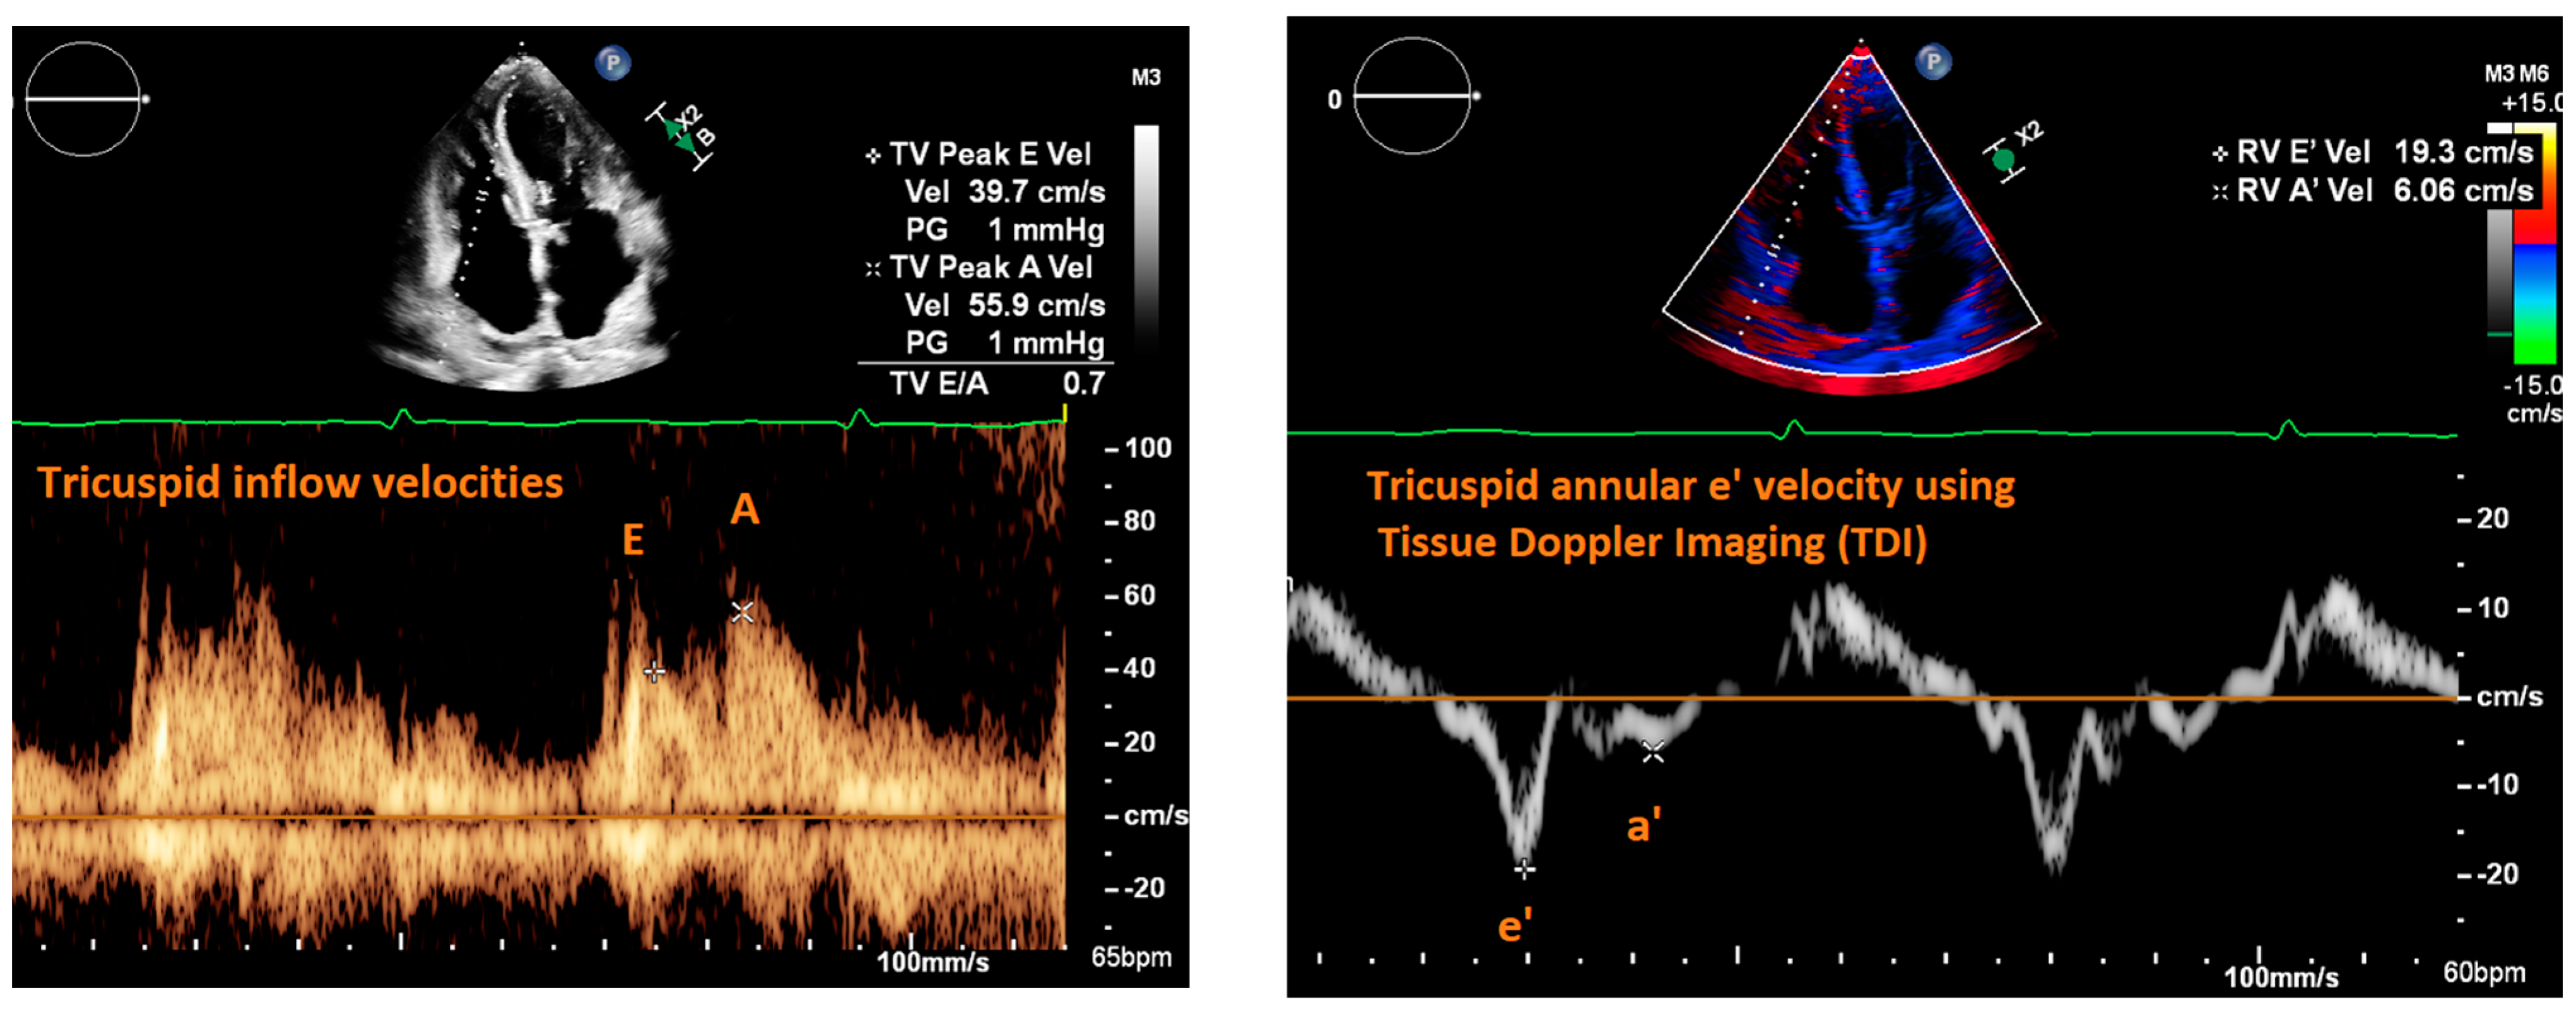

| Fletcher et al., 2020 [9] | Systematic review | Tricuspid inflow velocities | Patients with valvular disease, altered RV systolic function, recent cardiac surgery, acute heart failure, heart transplant, pulmonary hypertension, atrial fibrillation | Strength of correlation between E/e’ and RAP | 17 articles | Consistent positive correlation between E/e’ and RAP in patients with reduced RV systolic function; equivocal support correlating E/e’ and RAP in heart failure patients. |

| Mitral E/e’ ratio estimated from the E wave velocity of the mitral inflow Doppler envelope and the tissue Doppler e’ wave velocity at the mitral annulus (septal and/or lateral) | E/e’ ≤ 14 |

|

| |

| Peak velocity of the TR jet | ≤2/8 m/s |